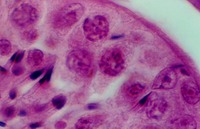

- Testes